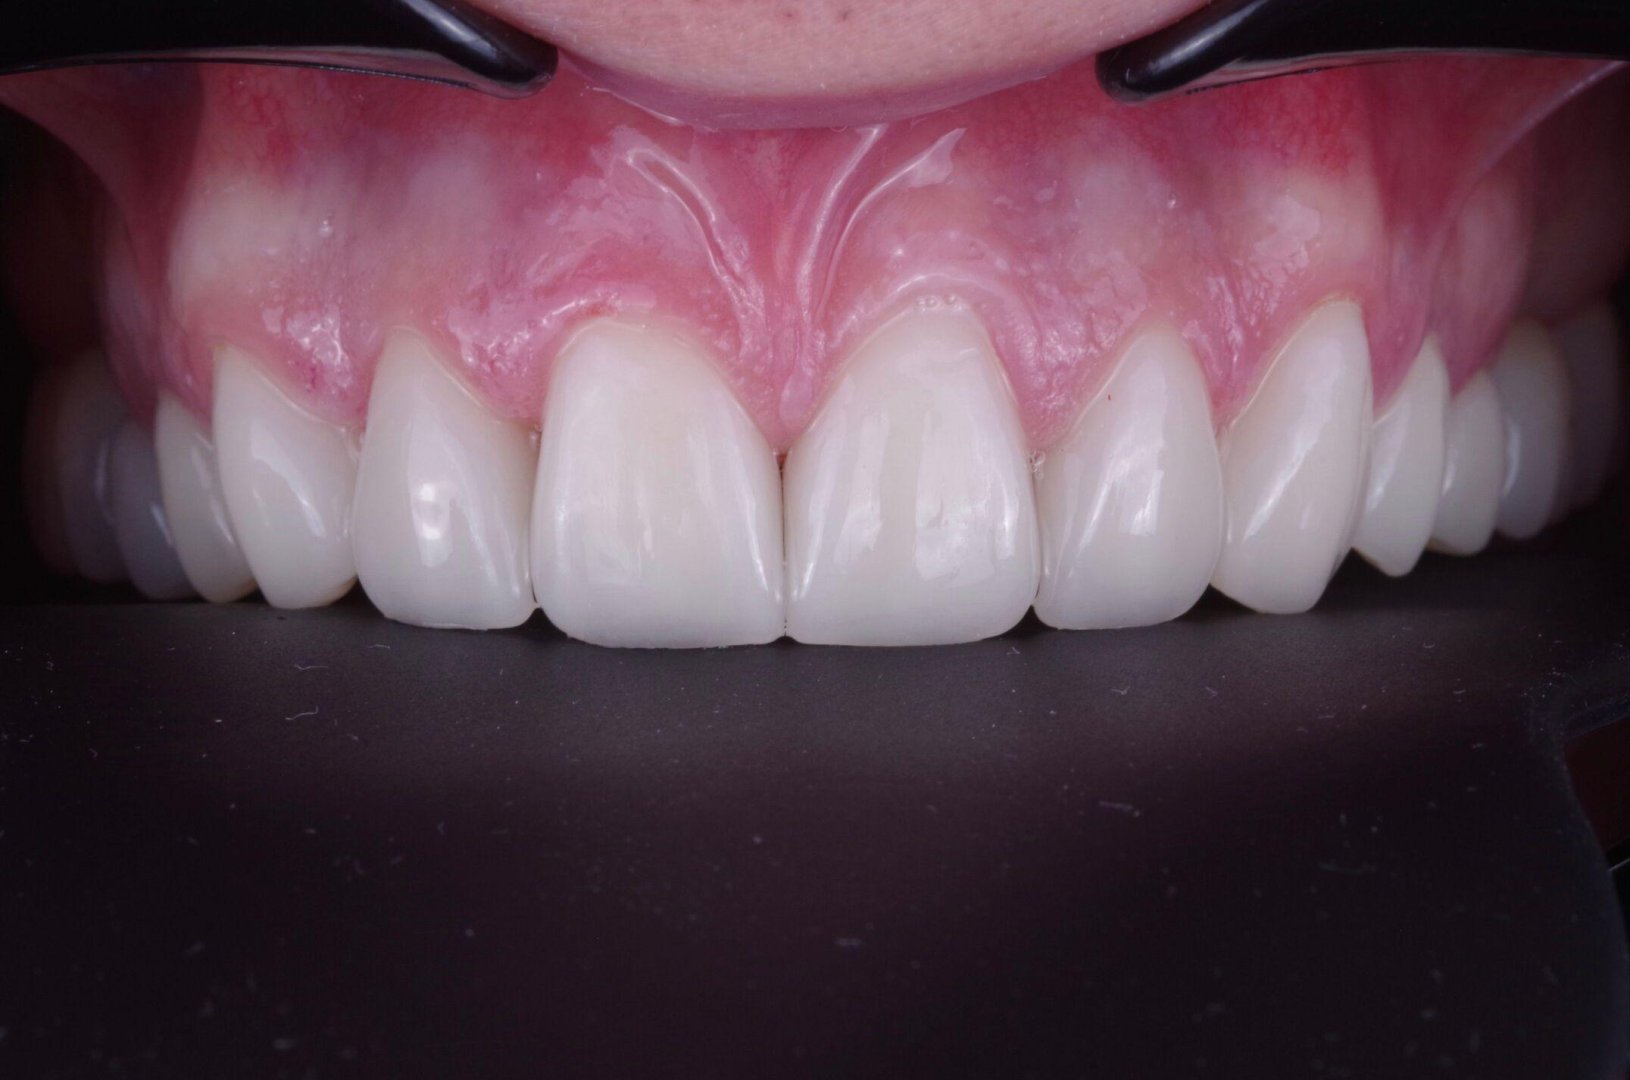

Преображение улыбки: виниры E.max (пример)

Тотальная реставрация зоны улыбки: задача — ровно, светло и при этом естественно. Обратите внимание на «живую» прозрачность и блеск — именно за это E.max любят.

ПОСЛЕ

Виниры E.max — после лечения

Виниры E.max — результат

Как выглядит «естественно»

Важно не просто «сделать белее». Важно попасть в форму, длину, наклон и прозрачность. E.max помогает передать глубину цвета и светопреломление — поэтому виниры не выглядят плоско.